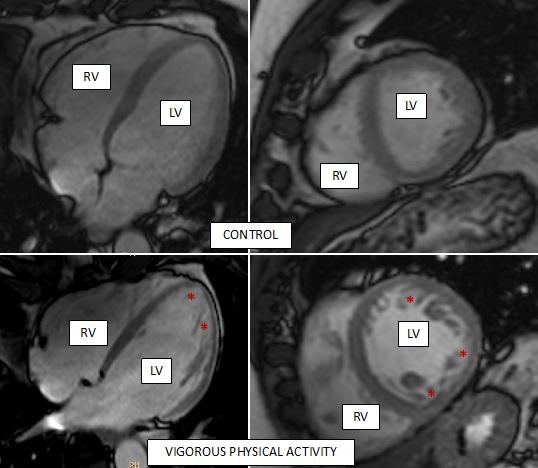

image: Representative cardiac magnetic resonance images of the hearts of two study participants, one control (top row) and one who does regular vigorous exercise (bottom row). Asterisks mark areas with trabeculae (spongy morphology) inside the left ventricle (LV) of the more active participant. RV, right ventricle.

Exercising regularly, whether intensely or moderately, is a health recommendation accepted by all experts. Nevertheless, high-intensity physical training can trigger a series of physiological changes in the body, including the heart. The hearts of professional athletes adapt to training in a number of ways, including by increasing the number of structures called trabeculae in the inside of the heart. While this process, called hypertrabeculation, is harmless in athletes, it is also a pathological feature of the hereditary disease noncompaction cardiomyopathy, which can cause sudden cardiac death.

The problem is that this disease is often diagnosed in young asymptomatic people, resulting in a medical recommendation to immediately cease physical activity that might cause sudden cardiac death. However, the presence of trabeculae is not always a sign of noncompacted cardiomyopathy. "Certain physiological situations, such as those resulting from high-intensity physical training or pregnancy, are known to trigger changes in heart structure similar to those seen in noncompacted cardiomyopathy," explained Dr Ibañez.

The association between hypertrabeculation and high-intensity physical activity in professional athletes was already known. The key innovation of the new study is its combination of cardiac magnetic resonance (the gold standard diagnostic method for analyzing heart structure and function) with objective measures of physical activity. "We previously lacked information about whether physiological hypertrabeculation occurs in the general population or is restricted to elite athletes," commented Dr Inés García-Lunar, an author on the study.

The study showed that participants who routinely did vigorous exercise during the study period had larger hearts with more muscle mass. "These changes are typical of 'athlete's heart' and are considered physiological," said García-Lunar.

A more surprising finding was that a third of participants with a high level of vigorous physical activity (both men and women) met the diagnostic criteria for noncompaction cardiomyopathy, even though they were obviously healthy.